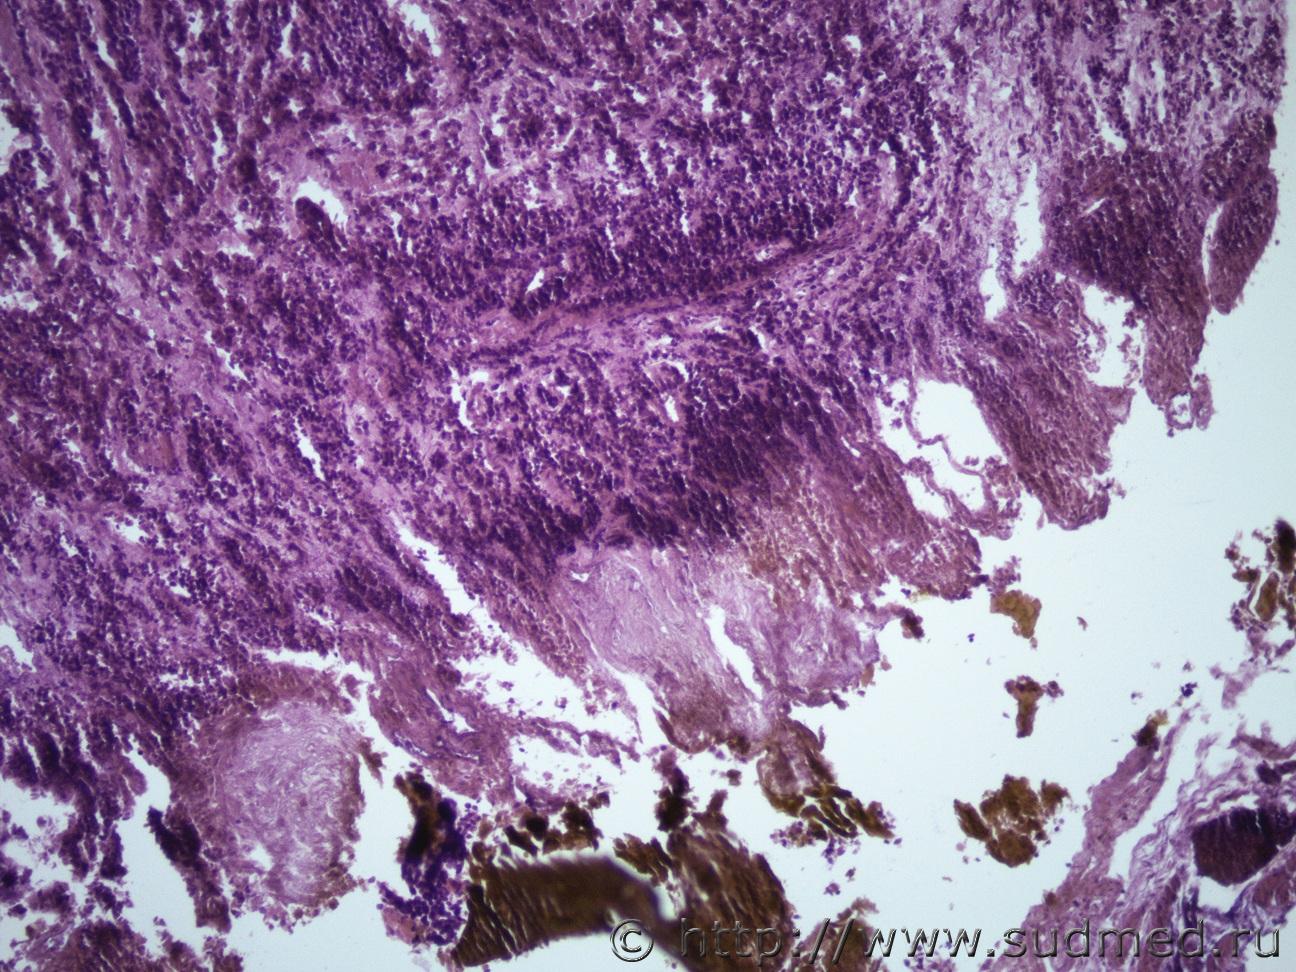

Ув. коллеги и снова здравствуйте. Как всегда опухоль. Макро- опухоль поджелудочной железы с прорастанием в окружающую клетчатку с метастазами в перибронхиальные, перипортальные ЛУ, в прикорневые отделы легких, в стенку желчного пузыря, тонкого кишечника. Легкие Судебная медицина - Прикрепленное изображение Судебная медицина - Прикрепленное изображениеСудебная медицина - Прикрепленное изображениеСудебная медицина - Прикрепленное изображение, перибрЛУСудебная медицина - Прикрепленное изображение ПЖ Судебная медицина - Прикрепленное изображениеСудебная медицина - Прикрепленное изображение , печеньСудебная медицина - Прикрепленное изображение Судебная медицина - Прикрепленное изображение Судебная медицина - Прикрепленное изображение Судебная медицина - Прикрепленное изображение Судебная медицина - Прикрепленное изображение, тонк кишСудебная медицина - Прикрепленное изображение

Наиболее подходит нейроэндокринный рак

Спасибо, рассмотрю этот вариант. Я все думала может НД протоковая аденокарцинома или мелкоклеточный рак.

Солидарен.

Непохоже.